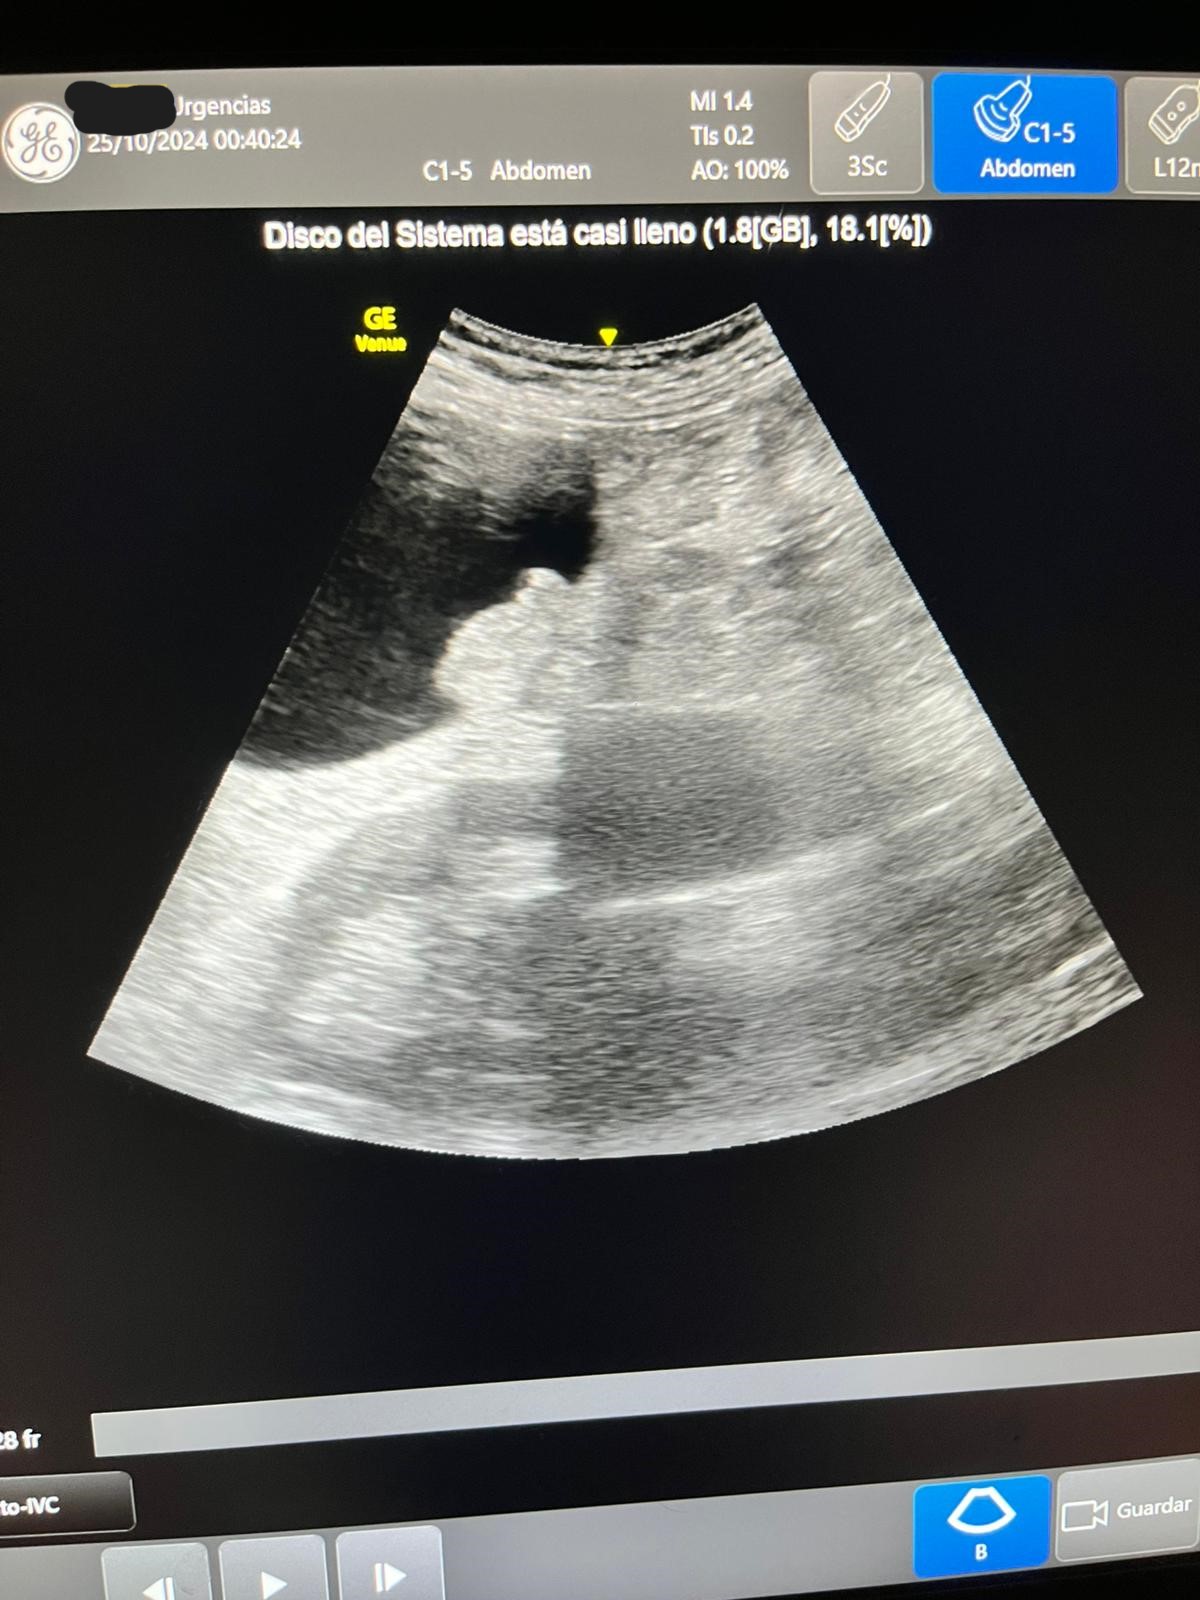

Ecografía: hígado y vías biliares normales sin formaciones expansivas. Coledoco de calibre normal.

Vesícula biliar distendida con litiasis múltiple suncentimétricas y barro biliar de paredes finas.

Páncreas y bazo sin alteraciones Riñones normales, sin dilatación de sistema excretor, urolitiasis ni lesiones expansivas sólidas. Quistes corticales simples en ambos riñones en tercio medio del izquierdo quiste complejo con tabiques finos y calcificación.